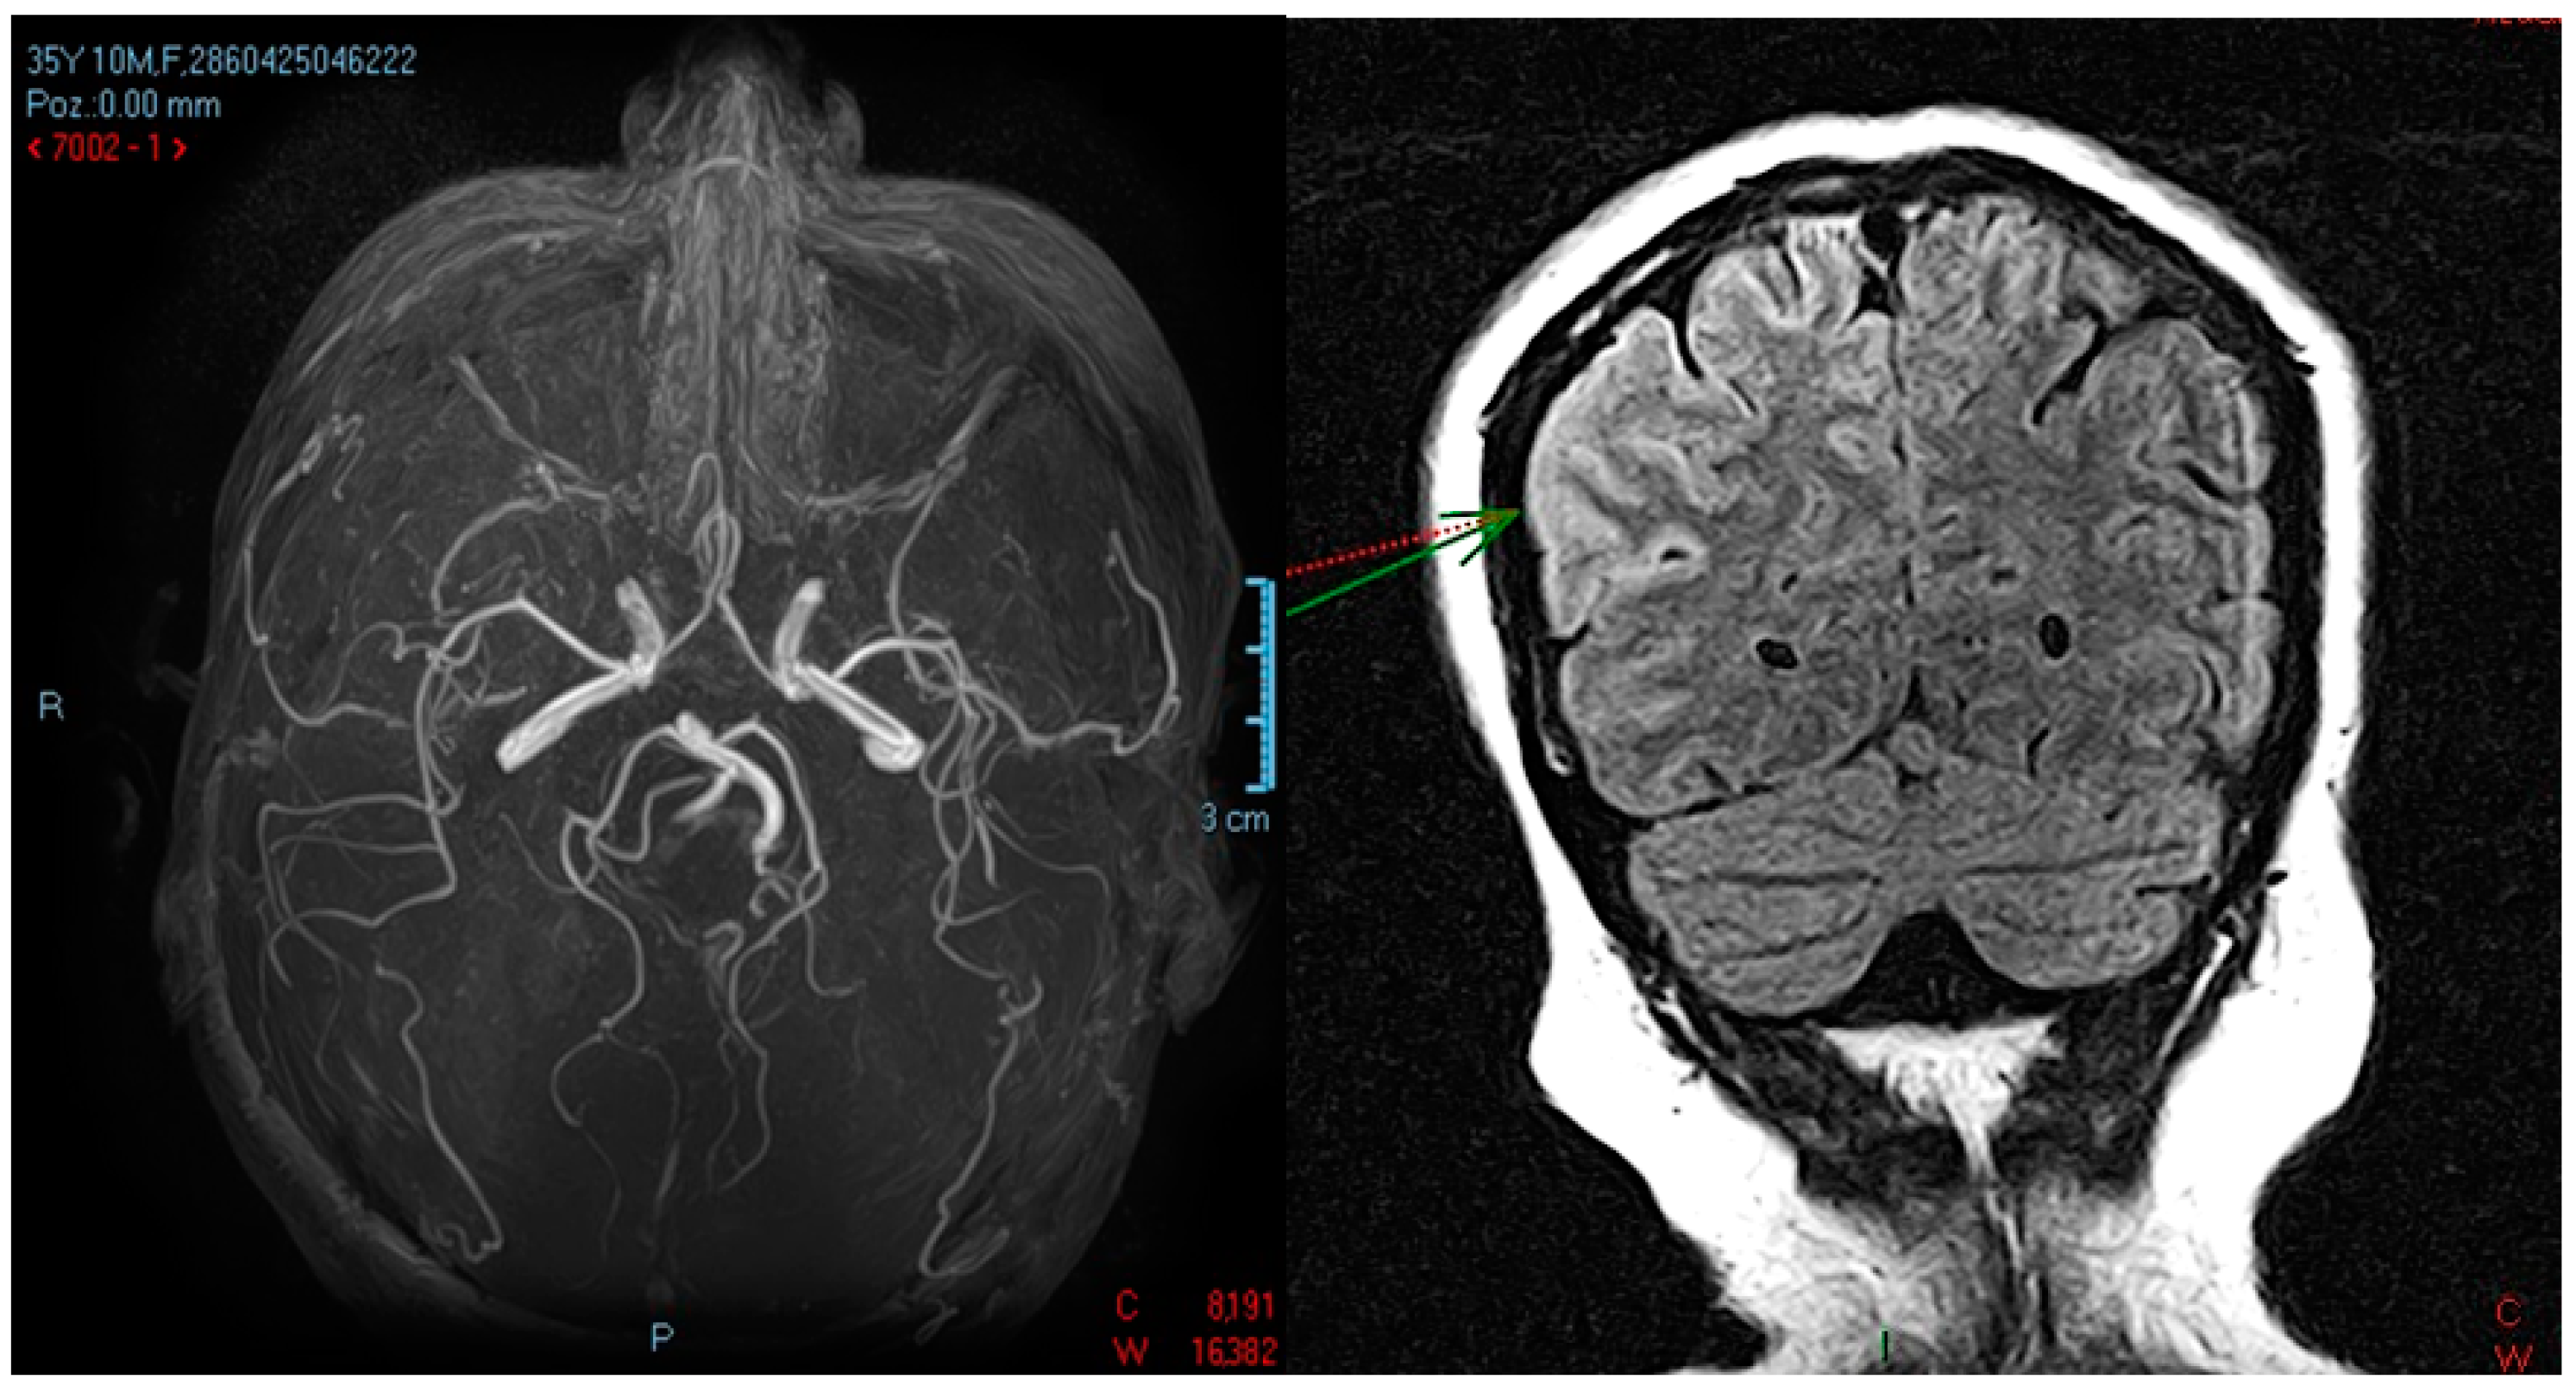

- a slight regression in the size and intensity of the T2 and FLAIR hyper signal, without restrictions on the diffusion sequence, not capturing the right temporo-occipital, associating a “swollen” aspect of the cortex with a slight erasure of the intergyral grooves, but without a mass effect on median line structures;

- small non-specific demyelinating lesions in hyper signal T2 and FLAIR, 2–4 mm, without diffusion sequence restriction, non-capturing, located in the frontoparietal subcortical and bilateral periventricular;

- no restrictions on the diffusion sequence, no hemorrhagic stigmata visible on the T2* sequence, no pathological intra/extra neuraxial contrast uptake or at the leptomeningeal level;

- normally positioned and sized ventricular system.